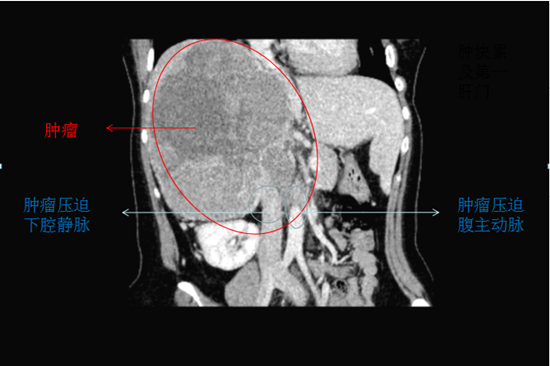

患者一個(gè)月前感覺右腰部脹痛,隨后出現(xiàn)雙下肢水腫,遂至當(dāng)?shù)蒯t(yī)院就診,檢查結(jié)果提示:右腎腫瘤并侵犯下腔靜脈,無法完成超高難度手術(shù),建議轉(zhuǎn)上級(jí)醫(yī)院治療。

轉(zhuǎn)至中南大學(xué)湘雅二醫(yī)院就診,急診科張東山教授聯(lián)合泌尿外科張磊副教授會(huì)診并為患者進(jìn)一步檢查,發(fā)現(xiàn)患者肝臟、腹膜后淋巴結(jié)、肝右靜脈及下腔靜脈都被侵犯并轉(zhuǎn)移。

患者右側(cè)肝腎間隙巨大腫塊及肝臟轉(zhuǎn)移灶緊臨右肝靜脈、壓迫下腔兩大主要靜脈及膽管,且兩大靜脈已被腫瘤侵犯,術(shù)中稍加不小心,隨時(shí)會(huì)造成大出血。右腎、右輸尿管受壓、積水,腹腔內(nèi)失去正常的解剖結(jié)構(gòu),加上患者既往有甲亢病史及高泌乳素血癥,對(duì)手術(shù)操作、麻醉及術(shù)后管理均提出了極大的挑戰(zhàn)。